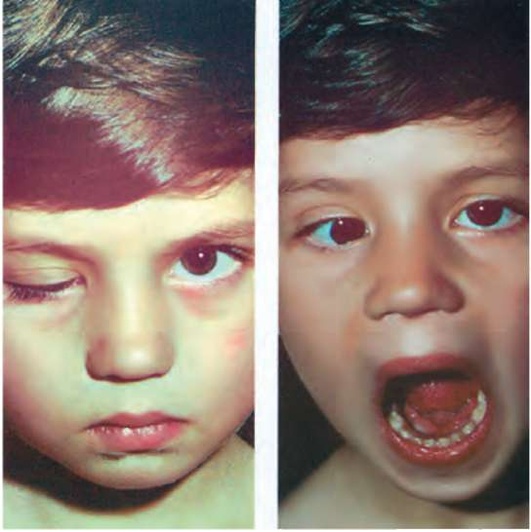

Рис. 9.2. Симптом Маркуса-Гунна. Пальпебрально-мандибулярная синкинезия: опущенное верхнее веко (птоз) спонтанно поднимается при открывании рта и отведении нижней челюсти